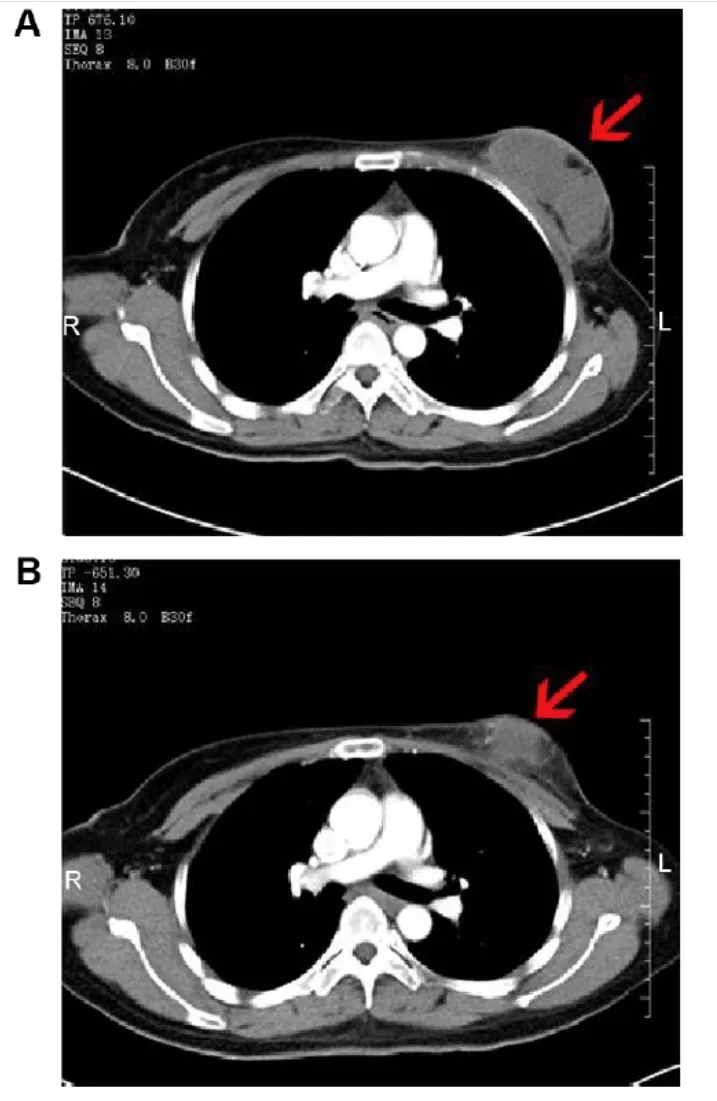

患者2:是一位57岁男性,患IVA期非小细胞肺癌(NSCLC),治疗前左肺下叶存在6.6×5.5×6.2cm肿块;治疗90天后肿瘤缩小至6.1×4.1×4.8cm(红色箭头示肿瘤位置)。

▲图源“JCI”,版权归原作者所有,如无意中侵犯了知识产权,请联系我们删除